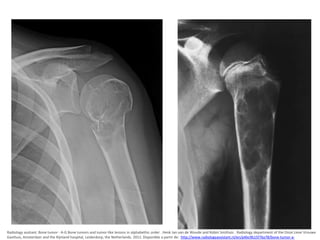

Osteocondroma

• Diagnostico por imágenes

– Aspecto puede ser sésil o pediculado.

– La cortical y medular del tumor se continúan con

las del hueso.

– los contornos están bien limitados y no presentan

ninguna imagen destructiva; el pedículo es

siempre opaco.

– Pediculado: La parte distal está a menudo

agrandada y puede mostrar un aspecto de gancho,

porra o coliflor.

Ortopedia y traumatologia. Silverman , Varaona. Editorial Medica Panamericana. 2da edicion . Pag. 205-219